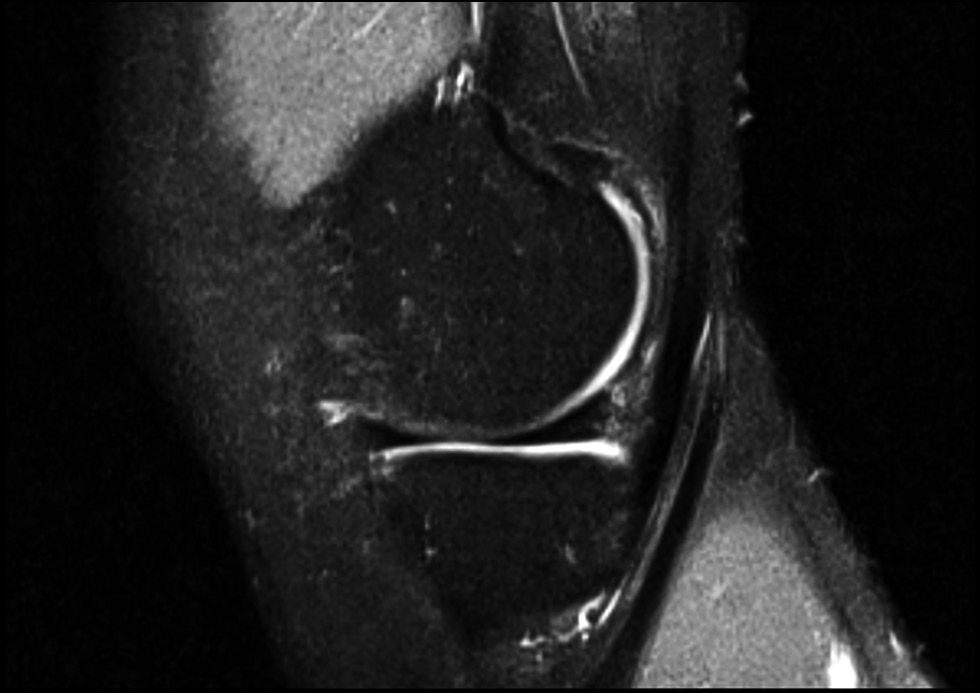

The results of treatment of patients are presented in Table 2 and in Figures 5 and 6. According to the VAS, Lequesne, Lysholm, KSS scales, and WOMAC index, all parameters improved, degree of pain syndrome decreased, and functional parameters increased.

Fig. 5. MRI of the patient before the platelet-rich plasma (PRP) procedure.